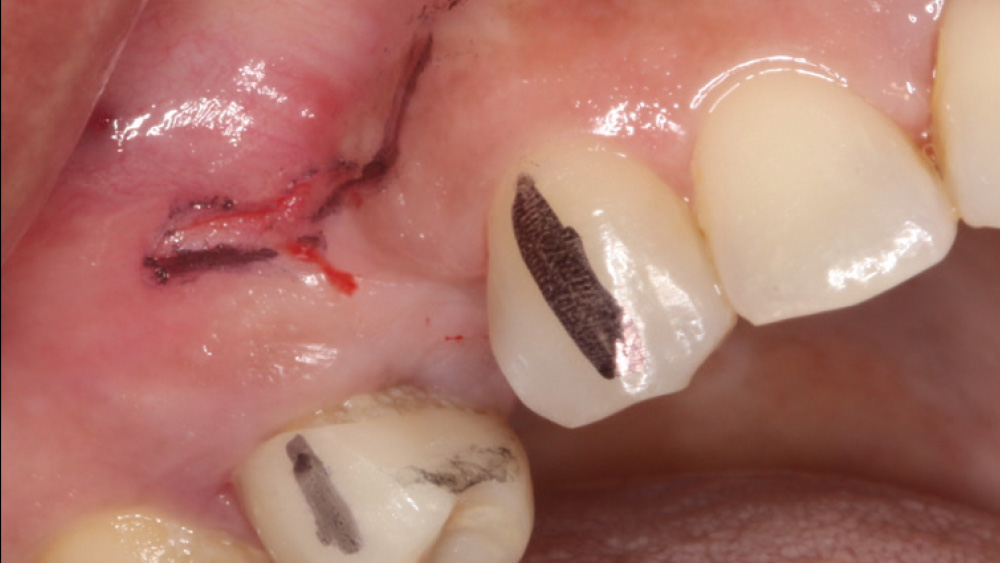

When the attached tissue is minimal, a flap procedure allows the surgeon to reposition the flap to create more attached gingiva and improve the interdental papillae at the implant site. Reflecting a gingival flap also enables the practitioner to more clearly see the final position of the implant at the crest of the bone. If it’s necessary to visualize the bone during the surgical procedure due to uncertain ridge width or height, flap reflection is the safest, most predictable approach.

The following case, which I performed alongside Dr. Stephanie Tilley of Pensacola, Florida, illustrates the use of both surgical techniques for the same patient, who presented with edentulous spaces in the areas of both right and left maxillary first bicuspids. Due to varying soft-tissue volume on each side of the arch, implant surgery was performed using a flapless procedure for one site, while the attached gingiva was reflected to expose the available hard tissue for the other. As a result of proper site evaluation, treatment planning and restorative-driven implant placement, both surgical techniques led to successful outcomes for the patient.